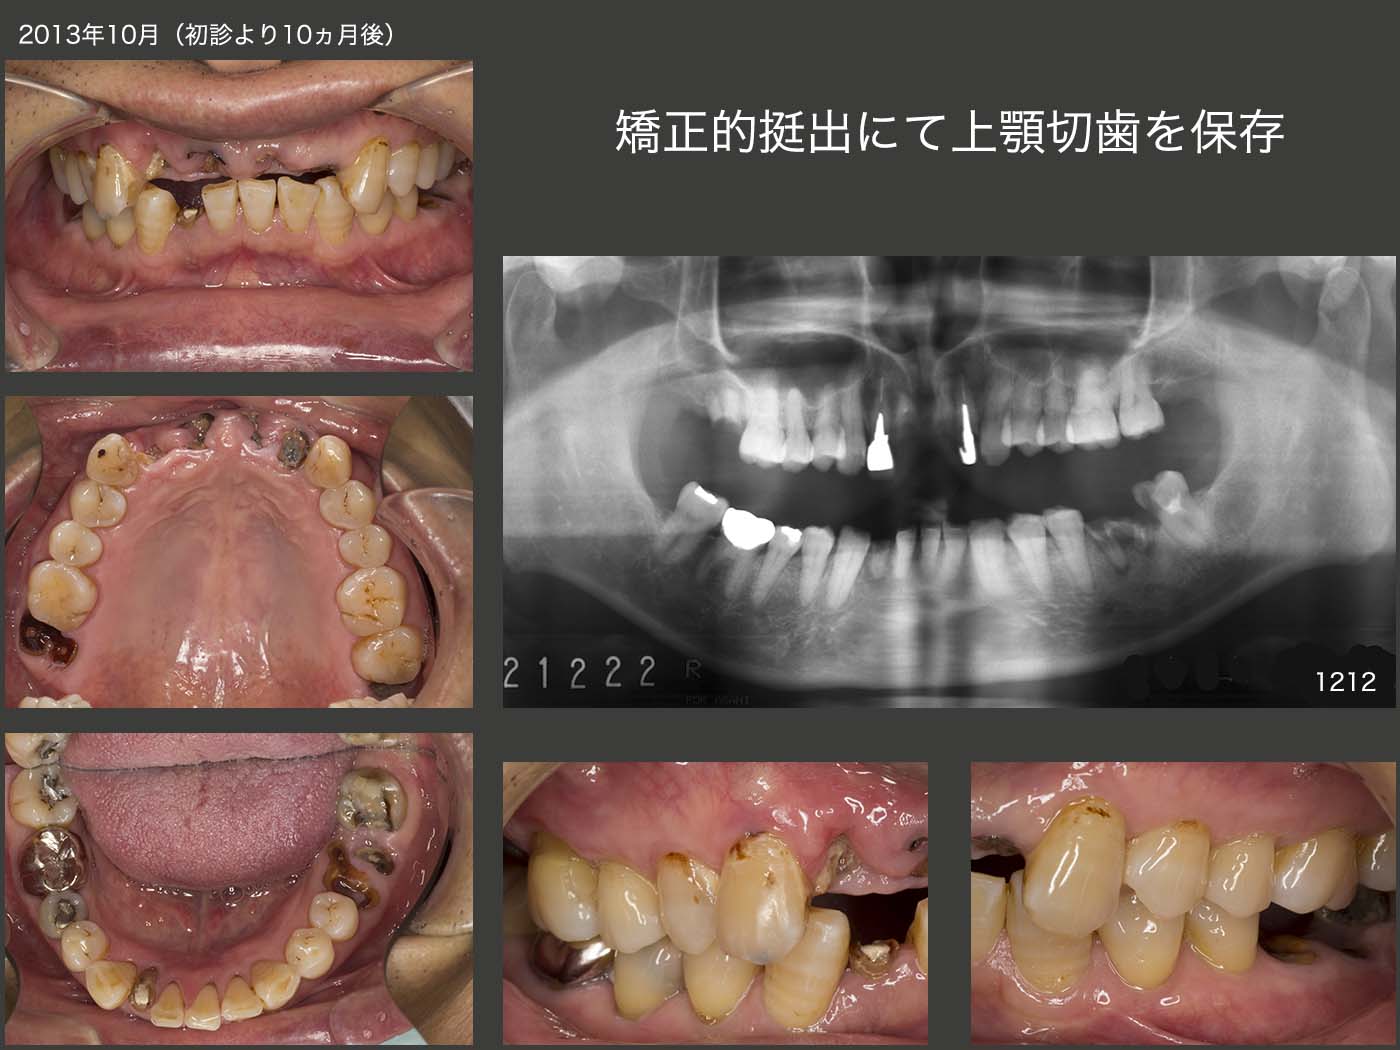

17.矯正的挻出にて上顎切歯を保存

2012年12月初診,60歳の男性.上顎中切歯の保存を希望しての来院であったが,さすがに保存不可能と判断した.その後来院が途絶えたが,13年10月に,上顎両側側切歯も脱落し,何とか治療して欲しいとのことで再来院した.兎に角,抜歯をして欲しくないとの強い希望があったので,保存が難しいと思われる上顎2〜2,右下2および右上7をとりあえず保存してみることにした.もちろん確約はできない旨をお伝えした.なお,左下6は抜歯ということで,ご理解して貰った.

2013年10月25日に,まず上顎左右側切歯の矯正的挻出を開始し,12月20日に終了した.14年1月22日に上顎2〜2の歯冠長延長術を行った.ここで,両側側切歯にコアを植立し,暫間被覆冠が外れにくくした.また,両側中切歯にもピッグテールが掛けられるようになったので,2月24日から中切歯の矯正的挻出を開始し,3月17日に終了した.3月29日に両側中切歯の歯冠長延長術を再度行い,歯肉縁上歯質を確保した.患者さんは,2から2の単独植立を希望された.しかし,両側中切歯の動揺が大きかったので,同部は連結固定することにし,一方両側側切歯の動揺は僅かであったので,単独植立することにした.ただ,前歯は審美優先で,ここで物を食いちぎることはできないし,絶対にしてはいけないと,来院のたびに力説した.